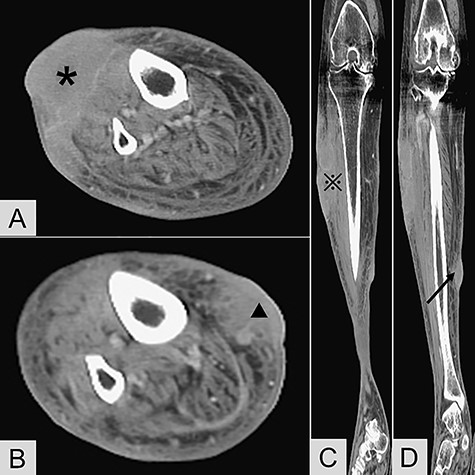

Physical examination revealed two red and violaceous skin lesions over the right lower leg, ~9 and 3 cm in size, respectively. The lesions were erythematous, had ill-defined borders and were tender on palpation. Local heat and swelling of the skin around the lesions were also noted. Laboratory data, including a complete blood count and biochemical studies, revealed no significant findings. Contrast-enhanced computed tomography of the lower limbs revealed an abnormal space-occupying lesion about 9 cm × 7.5 cm × 3.3 cm in size, at the anterior aspect of the right lower leg. It showed heterogeneous density, heterogeneous contrast enhancement, and involvement of the subcutaneous area, superficial fascial planes and muscle layer. Another small non-specific lesion about 3 cm in size was located at the medial aspect of the right lower leg, with similar radiological features (Fig. 1). With a provisional diagnosis of skin tumors with associated cellulitis of the right lower leg, she was subsequently admitted to our institution for further investigations and antibiotic treatment.

Contrast-enhanced computed tomography revealed (A) transverse view of the anterior lesion of right lower leg (*); (B) transverse view of the medial lesion of right lower leg (▲); (C) coronary view of the anterior lesion (

); (D) coronary view of the medial lesion (black arrow).